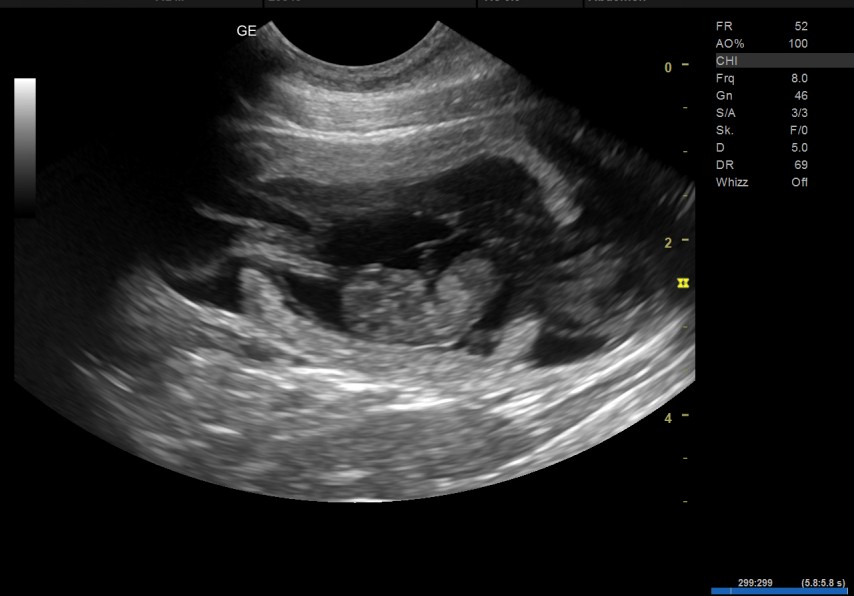

Gute Nachrichten: Die Ultraschall-Untersuchung am 24.04.2026 zeigt, dass in Juna Welpen heranwachsen! Der H-Wurf wird Ende Mai erwartet. Interessenten senden bitte eine E-Mail mit Telefonnummer an info (at) horizontcare.de